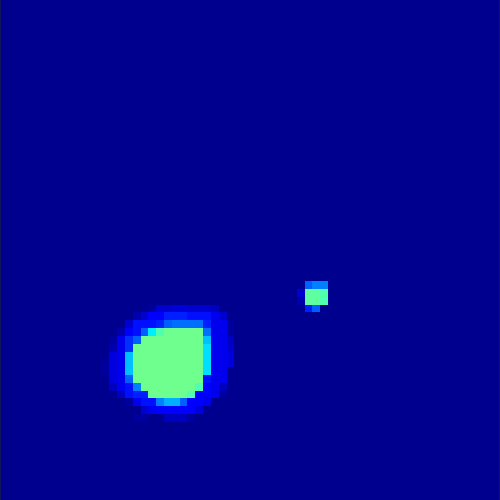

5.2 Monte Carlo Simulation

In order to test the behaviour of the proposed method in a more realistic, random-based test case, we performed a Monte Carlo simulation for dynamic SPECT imaging. First, we created a simple image phantom consisting of an outer and two inner circles which represents the structure of the region of interest (see figure 8(a)). Within those regions we assumed concentration curves over a time period of 90 time steps as displayed in figure 8(b). Based on the tracer intensity in an image frame at each time step, we created a variable number of random decay events (where the number is proportional to the average concentration in one pixel in the whole image frame per time step) with a probability proportional to the concentration in every subregion. They are detected by a virtual double head gamma camera rotating around the patient by 46 degrees per time step, which consists of 374 detector bins. Every simulated decay event is projected onto the scanner and counted by the corresponding detector bin.

In two different tests we fixed the number of events counted by the detector equal to (resp. ) times the average concentration in one pixel. The resulting sinogram images of the accumulated counts in each bin are shown in figure 9.

Based on the sinogram data we applied the proposed algorithm in order to reconstruct the original image sequence. The results for both test cases are shown in figure 10.

As one can see, the method is able to reconstruct the regions properly, even in case of a low count number. Within a number of iterations (average of 100 outer and 10000 inner iterations), the algorithm presents a reasonable reconstruction of the region of interest and the corresponding regional tracer concentration curves. Here, the parameters were not optimized as in the case of the synthesized data sets in the previous section, but kept fixed as , and . With futher optimized parameter values one could possibly provide even better results.